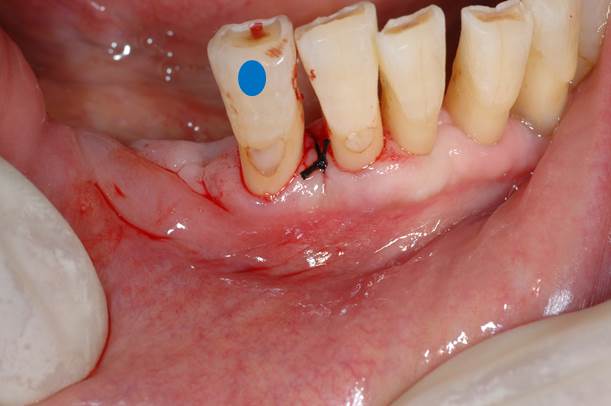

今回は歯周外科処置の中でも最も基本的なフラップ手術の紹介です。

青の歯のオレンジ部分に7mmの歯周ポケットが存在します。

歯肉を剥離して、掃除が終了した状態です。(オレンジの点線部分が失われた歯槽骨)

縫合が終了した状態です。